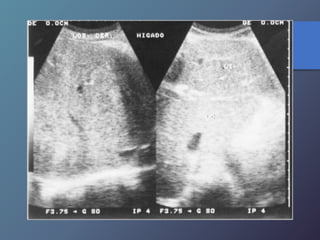

Hígado Graso

• Es un trastorno reversible del metabolismo.

• Acumulo de triglicéridos dentro del hepatocito.

• Causas: Obesidad, alcohol, hiperlipidemia mal

controlada, diabetes corticosteroides, etc.

• La infiltración grasa varia según la cantidad de grasa.

• Los depósitos pueden ser difusos o focales.

Difusos:

• Leve: Aumento mínimo de la ecogenicidad.

Visualización normal del diafragma.

• Moderada: Aumento moderado de la ecogenicidad

perdida ligera de la visualización del diafragma.

• Grave: Aumento acentuado de la ecogenicidad,

mala visualización o ninguna del diafragma.

Focales:

• Pueden parecer afectación neoplásica.

• Suelen ser redondas con bordes geométricos.